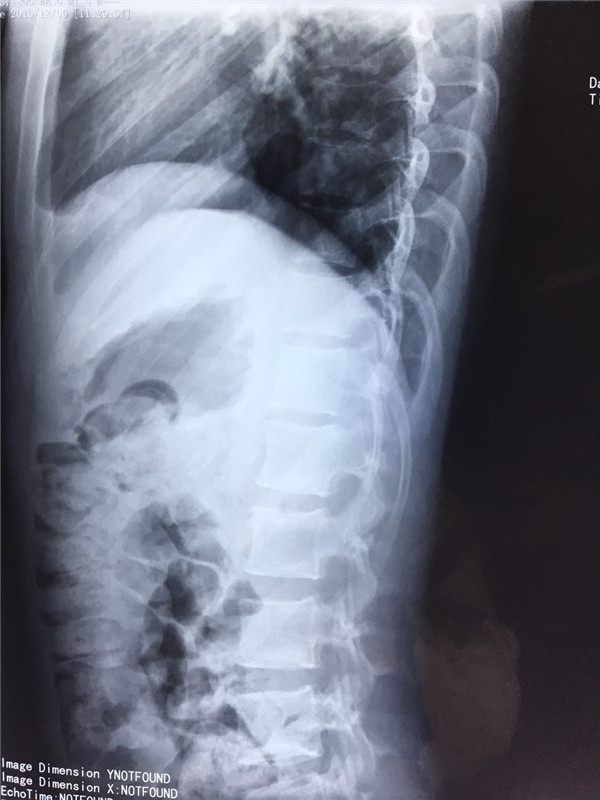

术前 侧位